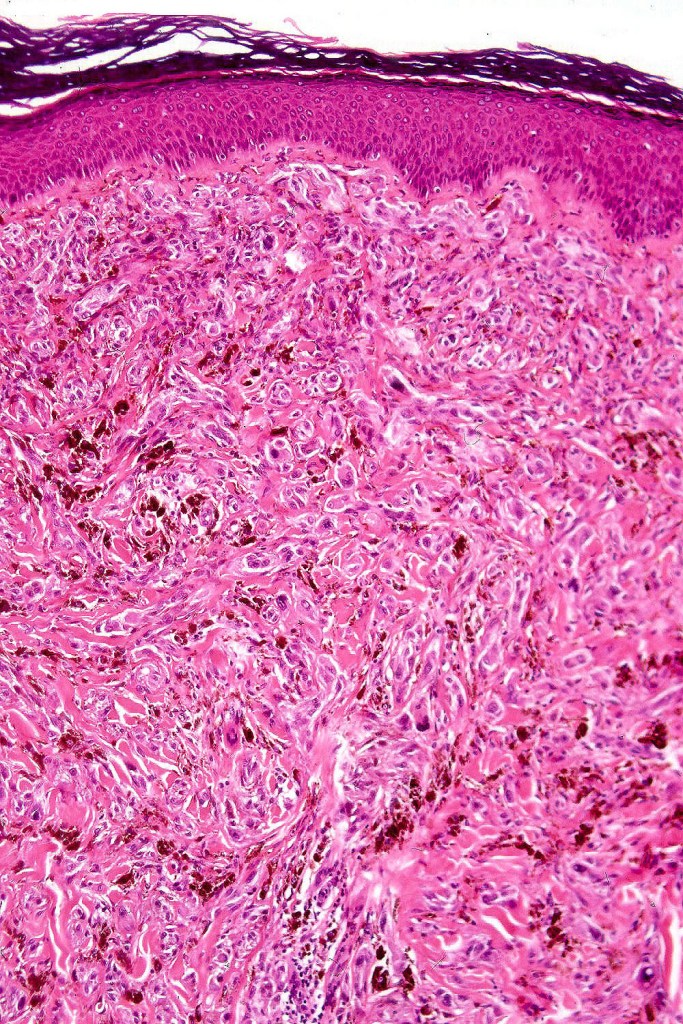

Histological features

•Most characteristic is the dumbbell silhouette although a plague morphology may also be encountered

•Admixture of spindle cells, pigmented bipolar or dendritic cells & melanophages

•An alveolar pattern is characteristic particularly with clear cell nodules

•Multinucleate giant cells sometimes present

•Stromal fibrosis, myxoid change, vascular hyalinization with cyst formation are often seen

•Some tumors are composed spindle cells in a fascicular or neuronevoid pattern